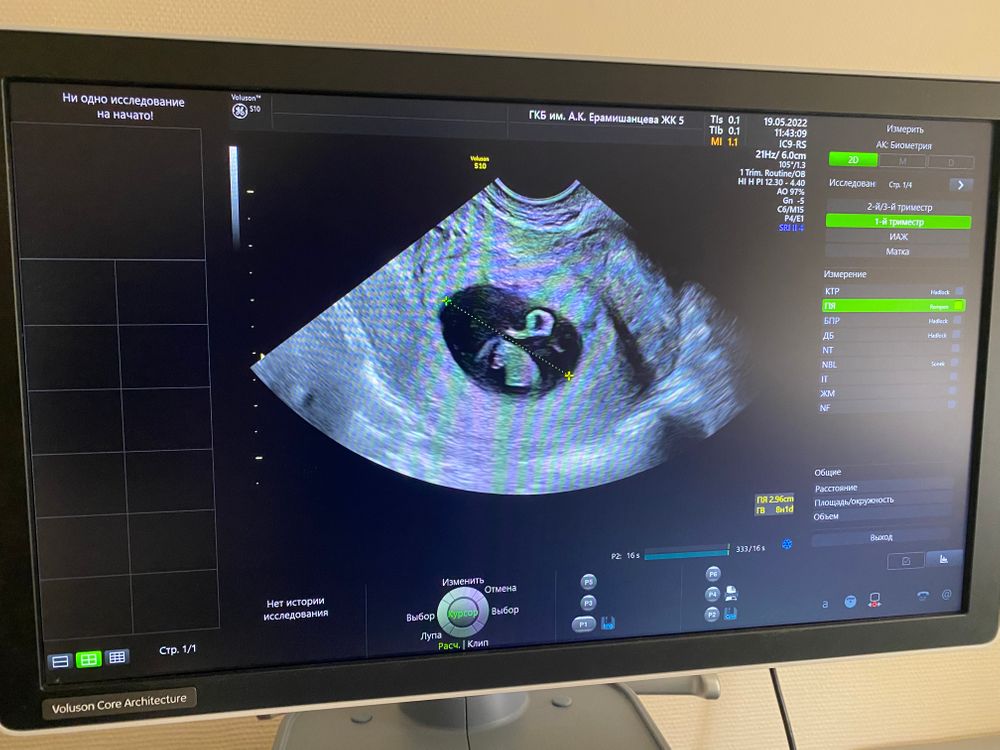

УЗИ 5+6, не соответствует сроку....

Изображение Вот мое узи от 3 мая ,а вот фото при постановке на учёт )В четверг уже на первый скрининг )Токсикоз ,сонливость ,все «прелести» счастливой беременности )Не переживайте ,у меня 2 ЗБ в прошлом,но я все равно верила в хорошее) Изображение

Всмысле не соответствует?Все у вас по сроку, у меня в 6+2 ктр 5 мм был и все по сроку,то есть если взять что эмбрион растет 1 мм в сутки,то в 5+6 у меня тоже был бы 2 мм и срок по месячным у меня был точный, овуляция отслежена,да и заключение у вас стоит беременность 5+5 тоесть разница в 1 день с вашим сроком,откуда может быть ктр -5?

Марина, сказала маленьким 2 мм ещё и не четким, что на таком сроке должно быть ❤️

Ylia, при 2 мм не каждый аппарат сб может найти, так-то у вас все по сроку